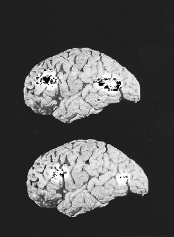

Два

мозга были подвергнуты томографическому

исследованию. На верхнем снимке - мозг,

страдающий от депрессии, у него больший

объем занимают затронутые болезнью

участки (они отмечены бело-черными

пятнами). На нижнем снимке - здоровый

мозг.